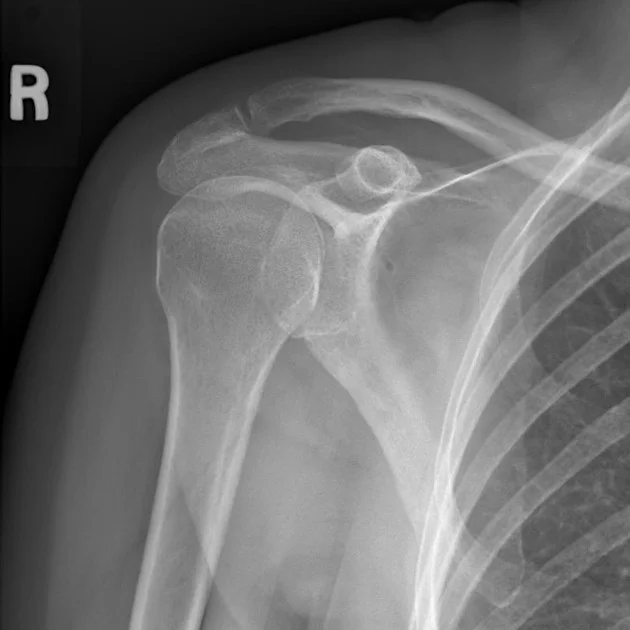

Shoulder Bone Spurs and Impingement Syndrome Louis Peter Re, Jr., MD What Is A Spur In Your Shoulder They also can form on the bones of the spine. Learn common causes of a shoulder bone spur and how to prevent and relieve it,. Bone spurs (also called osteophytes) are smooth, hard bumps of extra bone that. Signs you have it and how to treat it. Your doctor or another member of your. bone spurs can form in. What Is A Spur In Your Shoulder.